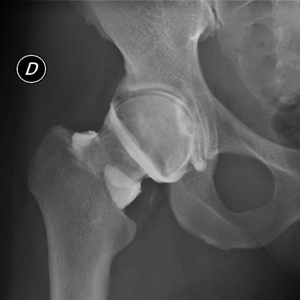

Le principe d’une infiltration est d’injecter au sein d’une articulation, d’une gaine tendineuse ou du canal lombaire des corticoïdes visant à diminuer l’inflammation locale. Le produit étant ainsi très concentré localement, le principe est plus actif que les anti‑inflammatoires pris par voie orale.